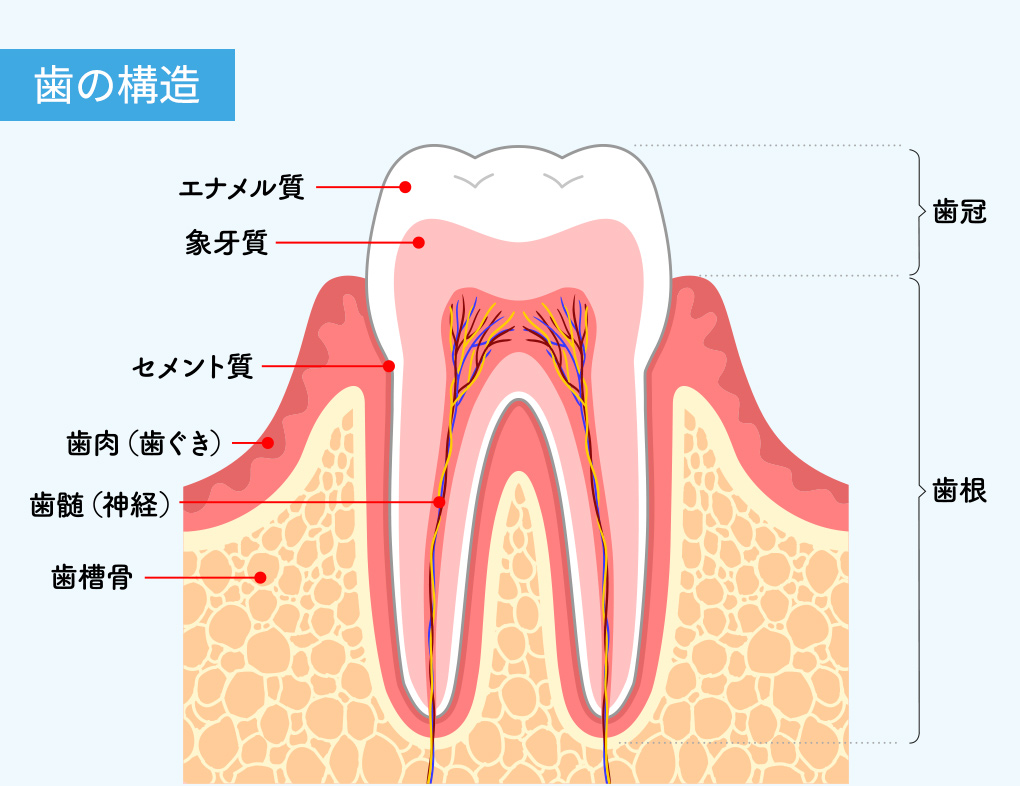

歯は歯肉から見えている「歯冠部」と歯肉から下の「歯根部」でできています。この構造から、歯を長く維持するためには、見えている歯だけではなく、歯を歯根から支える歯肉や歯槽骨を含む歯周組織もケアが重要だとわかります。歯、歯周組織を正常に守るため、細菌が少なく清潔な口腔環境の維持が求められます。